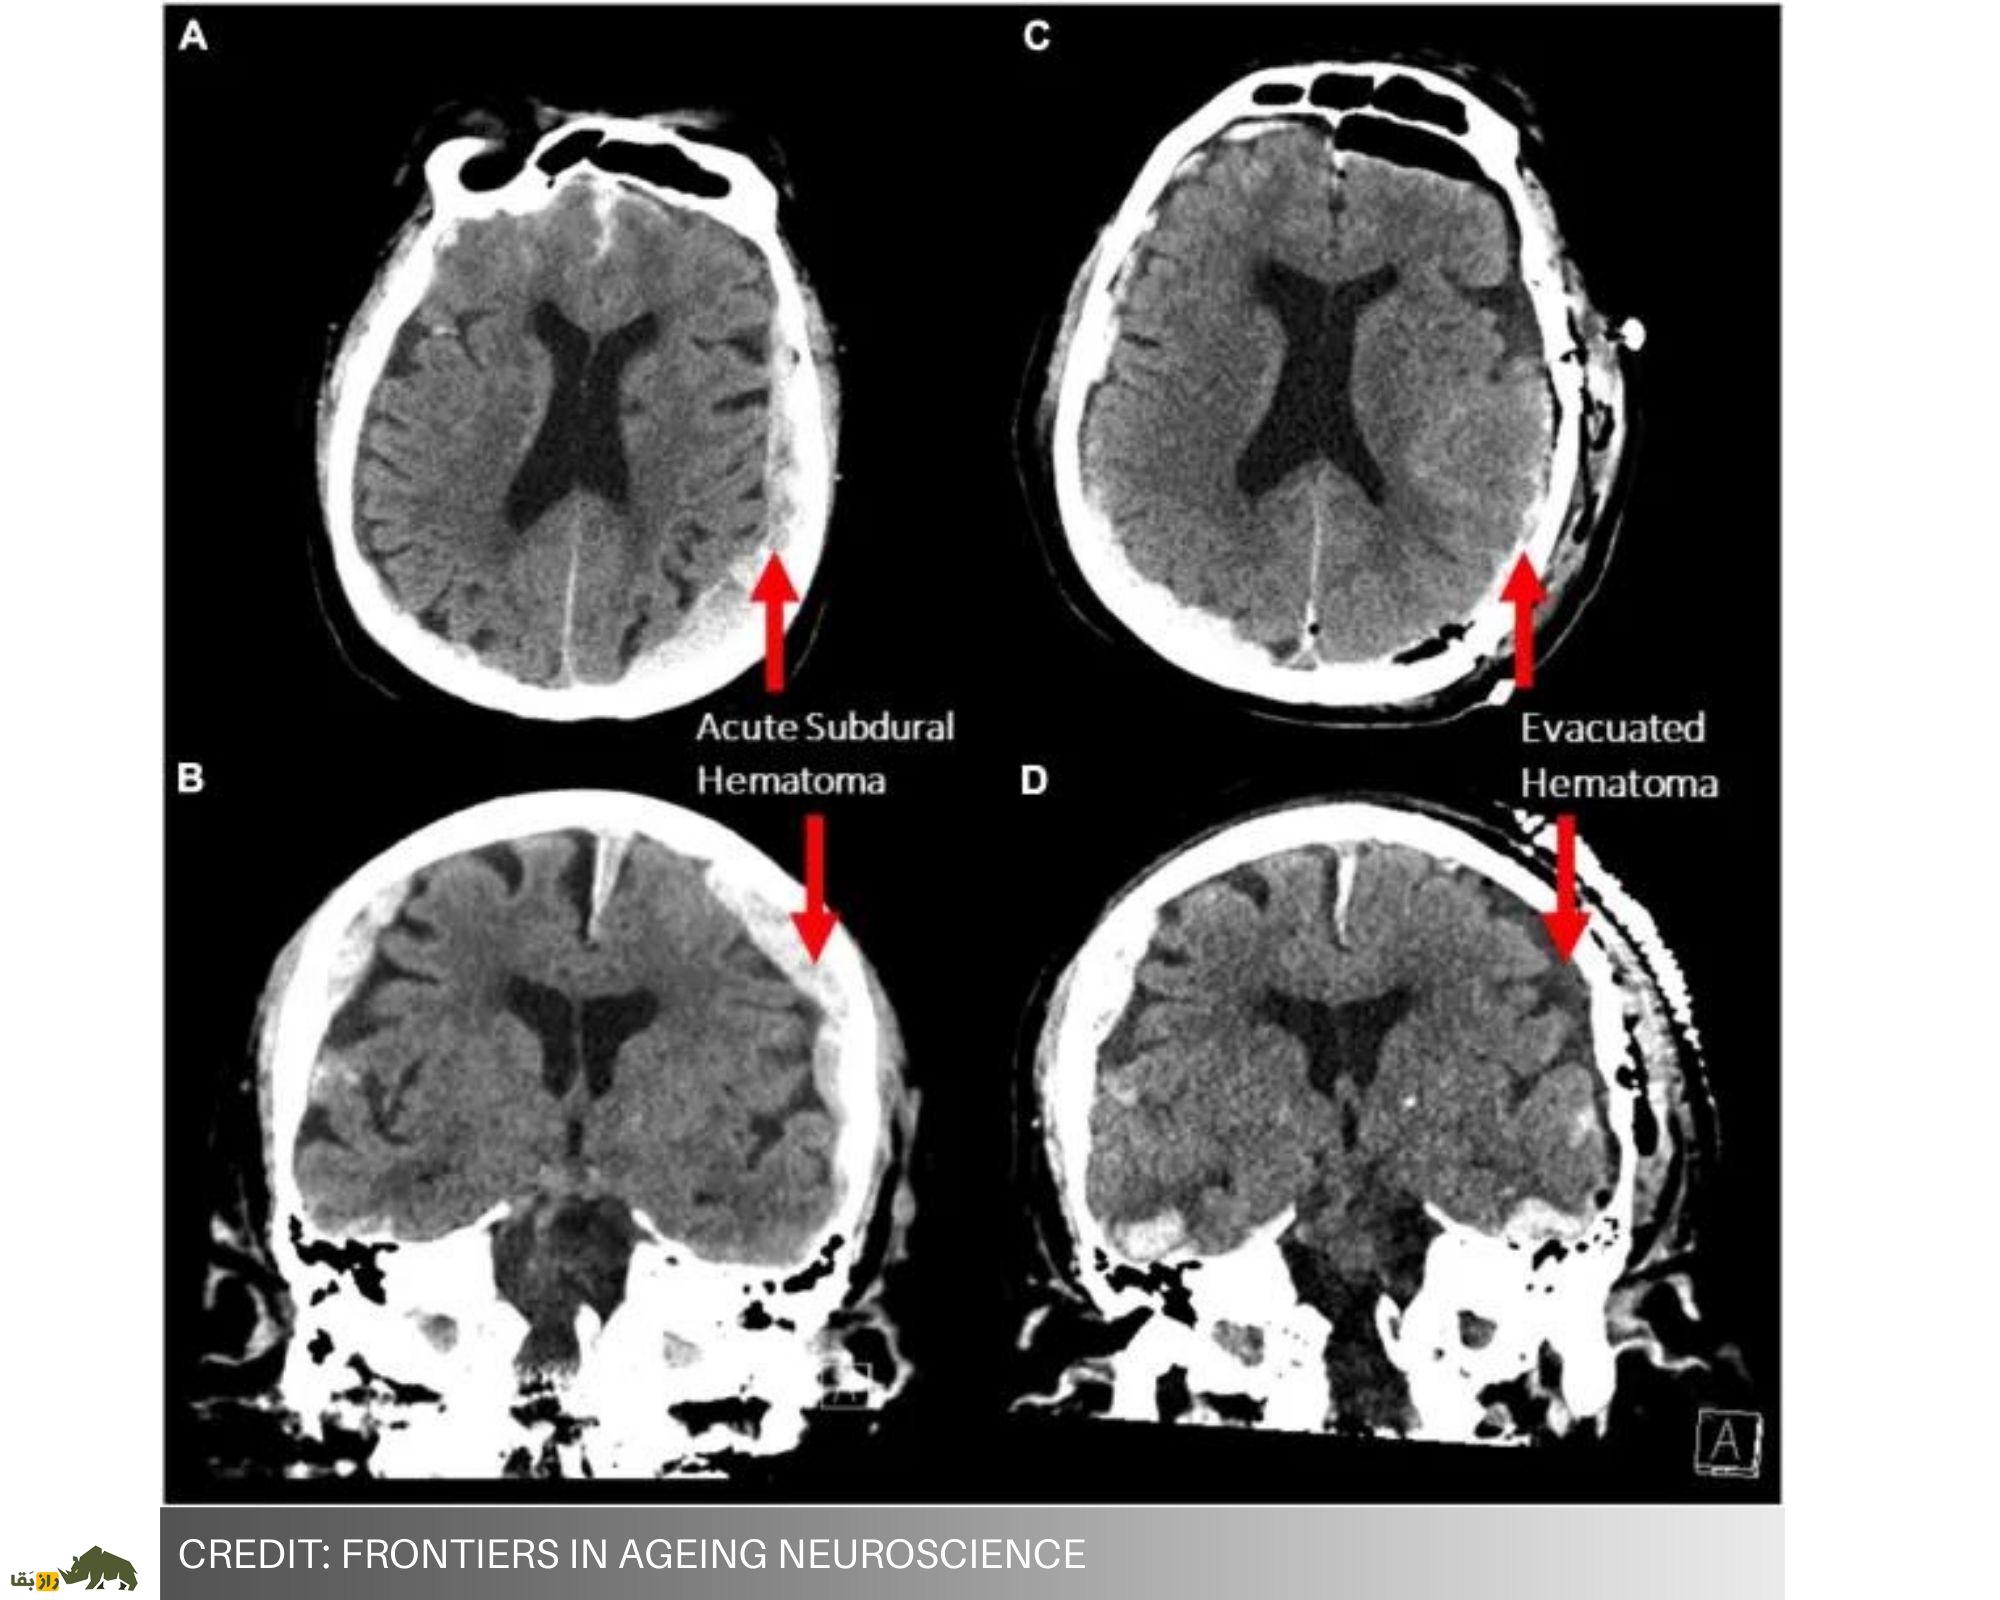

تحقیقات منتشر شده نشان داد که فرآیند مرگ ممکن است بسیار خوشایندتر از آنچه ما فکر میکنیم باشد. دانشمندان بهطور تصادفی تصاویری از مغز، پیچیدهترین اندام ما، هنگام خاموش شدن ضبط کردند و به این ترتیب چشماندازی شگفتانگیز از مرگ را به دست آوردند.

یک بیمار مبتلا به صرع قبل از حمله قلبی به یک دستگاه نوار مغزی (EEG) متصل شده بود.

این بدان معنا بود که ۱۵ دقیقه حول و حوش زمان مرگ او در نوار مغزی ثبت شده است. در ۳۰ ثانیه قبل و بعد از آخرین ضربان قلب بیمار، افزایش امواج مغزی بسیار خاص مشاهده شد.